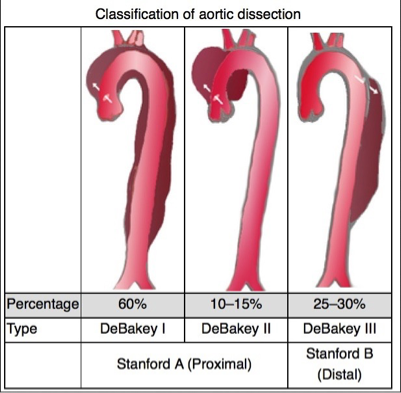

What does this refer to (in terms of aortic dissection)

Most simplified classification system EVER!

Stanford system divided into:

Stanford Type A (proximal)

_______________

Involves the Ascending aorta

What does this refer to (in terms of aortic dissection)

Most simplified classification system EVER!

Stanford system divided into:

Stanford Type B (distal)

__________

Does NOT involve the ascending aorta

What does this refer to

Stanford Typing System Aortic Dissection

Tx choice often depends on location

Stanford type A (ascending aortic) dissection

Immediate Open surgical mgmt superior to medical mgmt

Uncomplicated Stanford type B (distal aortic)

Medical mgmt preferred over surgical intervention

Repair if evidence of rupture or vessel occlusion

Medical management of aortic dissection